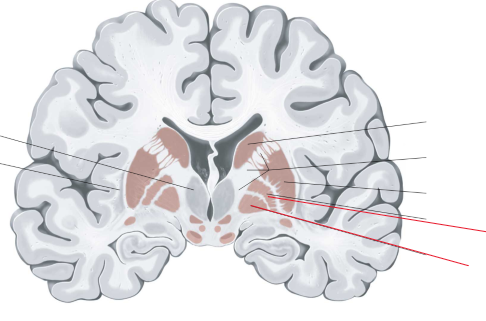

nucleus caudatus

putamen

globus pallidus

capsula interna (corona radiata)

capsula externa

capsula extrema

hippocampus

amygdala

laterale ventrikels (I en II)

septum pellucidum